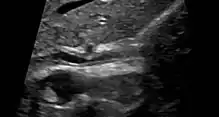

Various forms of gallbladder disease such as gallstones and gallbladder polyps are also common in those with PSC.[1] Approximately 25% of people with PSC have gallstones.[1] Ultrasound surveillance of the gallbladder every year is recommended for people with PSC.[1] Any person with PSC who is found to have a mass in the gallbladder should undergo surgical removal of the gallbladder due to the high risk of cholangiocarcinoma.[1] Osteoporosis (hepatic osteodystrophy) and hypothyroidism are also associated with PSC.